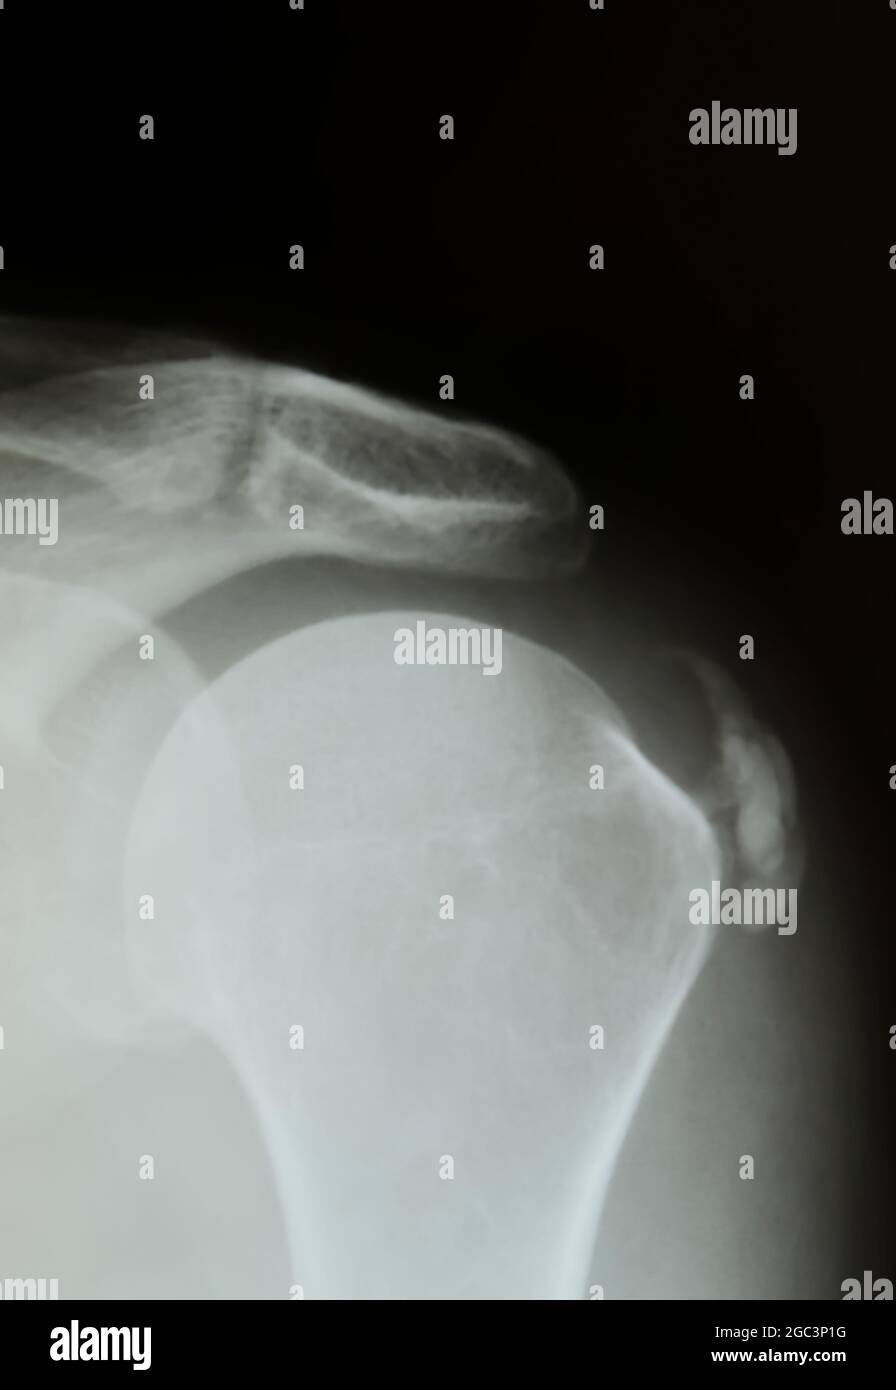

Shoulder Xray Of Peritendinitis Calcarea Stock Photo Download Image X Ray Shoulder Calcification calcific tendinopathy is a disorder of the shoulder of unknown etiology characterized by the formation of deposits. calcific tendonitis is the calcification and tendon degeneration near the rotator cuff insertion, most commonly leading to. anteroposterior cr of the left shoulder (b) performed 3 days later reveals a large calcification over the humeral head. after checking your. X Ray Shoulder Calcification.